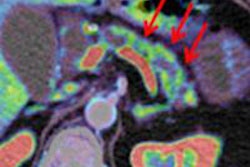

The treatment, which uses microsecond electrical pulses to force open and destroy tumor cells around blood vessels of the pancreas, was used to treat eight patients at the University of Miami Miller School of Medicine between December 2010 and September 2011. The patients received the interventional radiology treatment a median of nine months after being diagnosed. They also underwent two other methods of treatment to kill their cancerous tumors, which ranged from 2.5 to 6.8 cm in size.

Dr. Govindarajan Narayanan, chief of vascular and interventional radiology and associate professor of clinical radiology at the university, said that two of the patients were able to have surgery after the treatment; they had successful resections and remain cancer-free.